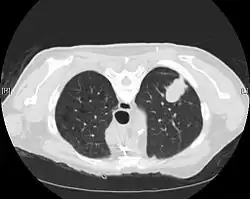

Imaging

CT imaging provides better evaluation of the lungs, with higher sensitivity and specificity for lung cancer compared to chest radiograph (although still significant false positive rate[27]). Computed tomography (CT) that is specifically aimed at evaluating lung cancer includes the chest and the upper abdomen. This allows for evaluation of other relevant anatomic structures such as nearby lymph nodes, adrenal glands, liver, and bones which may show evidence of metastatic spread of disease.[4] Indeed, the US Preventative Services Task Force recommends annual screening with low-dose CT in adults aged 55 to 80 years who have a 30 pack-year smoking history and currently smoke or have quit within the past 15 years, with certain caveats (see Lung cancer screening).[28]

Nuclear medicine imaging, such as PET/CT and bone scan, may also be helpful to diagnose and detect metastatic disease elsewhere in the body.[7] PET/CT uses a metabolically active tracer that allows clinicians to identify areas of the body that are hypermetabolic. Increased uptake of the tracer occurs in malignant cells and areas of inflammation or infection. Integrating the imaging reflective of metabolic activity with normal CT imaging allows for higher sensitivity and specificity compared to PET alone.[4]

MRI is reserved for patients with advanced disease where intracranial, or brain, involvement is likely. It is also helpful for evaluating the extent of chest wall, diaphragmatic, brachial plexus (such as in the case of superior sulcus tumors), or spine involvement.[4]